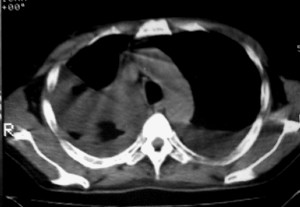

右侧肺癌术后:肝内可见多个大小不等的低密度结节影。腹腔及双侧胸腔大量积液。考虑:肺癌并胸膜及肝脏转移。

纵隔淋巴结增大,双侧胸水。考虑术后残留,而非复发。

肺癌术后 。双侧胸水 纵隔 胸膜 肝脏转移